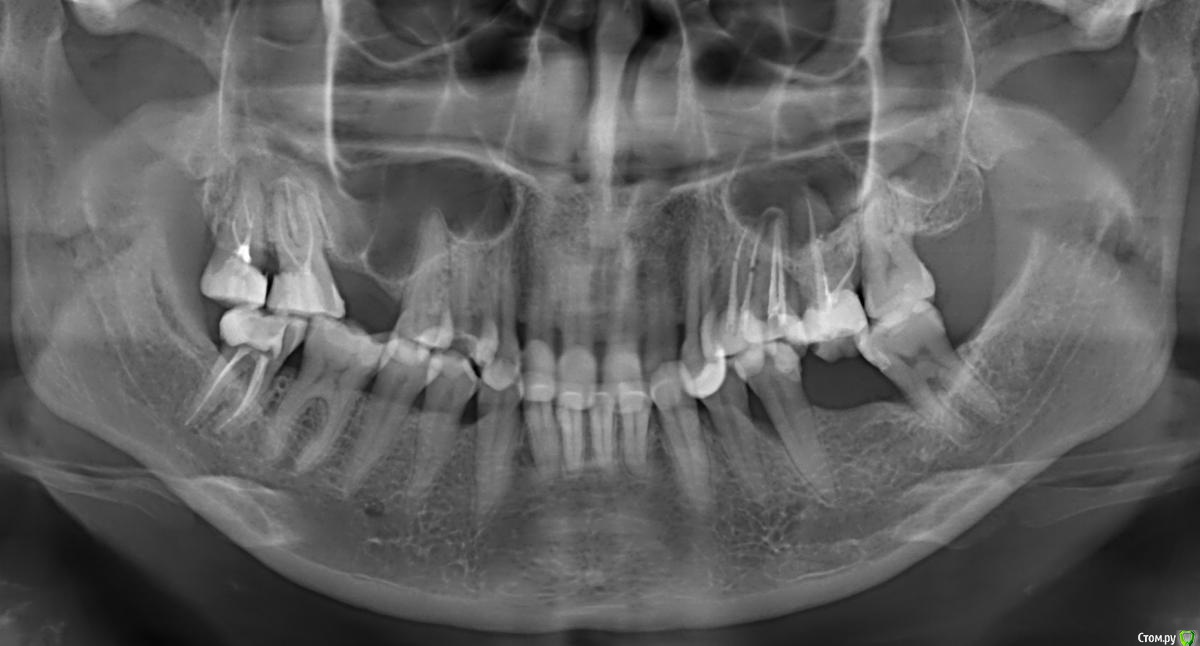

Нади999 Опубликовано 2 июня, 2015 Поделиться Опубликовано 2 июня, 2015 Помогите, пожалуйста с планом лечения и выбором специалистов: 1. Снижен прикус (2-3 мм.). 5 месяцев ношу капу (на ночь) для проверки реакции ВНЧС - с капой комфортно. - Возможно ли поднять прикус на 2 мм. на имплантах + пломбировочный материал или возможен только вариант импланты + коронки? 2. Проблема на верхней челюсти (7,8 на снимке слева). Образовалось киста. На месте предполагаемой имплантации (6-ка слева на снимке) недостаточно костного материала мене 1 мм. -Возможно ли сохранить последние зубы на верхней челюсти (7,8 на снимке слева) и сделать синус-лифтинг только на месте 6-го верхнего зуба. Или необходимо удалить последние, выждать время, сделать синус-лифтинг над гайморовой пазухой и поставить 2 импланта. Будут ли держаться!? 3. На нижней челюсти отсутствует зуб справа на снимке.Достаточно ли кости для имплантации? Могли бы посоветовать хороших специалистов с успешной практикой (не начинающих) по доступным ценам, к которым можно обратится по этим вопросам. Нужна ли в моем случае консультация Гнатолога!? P.S.Заранее приношу извинение за возможную некорректную нумерацию зубов - я не стоматолог!)))Благодарю за помощь! Ссылка на комментарий